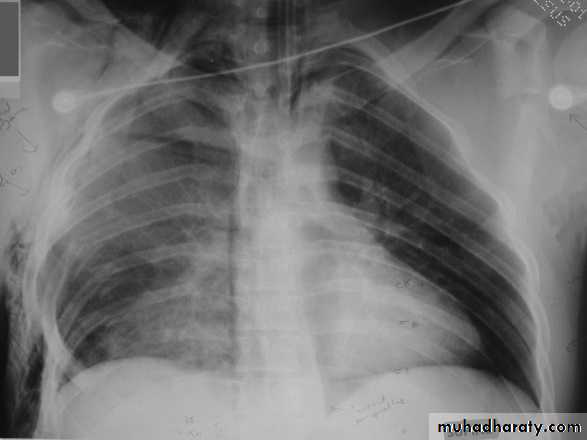

X-ray hemothorax

X-ray pneumohemothorax